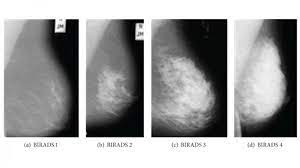

What Does Cancer Look Like On Mammogram : Mammography 3d Mammography Tomosynthesis Densebreast Info Inc / The rate of breast cancers discovered as dcis is thought to be increasing, but this is partially a testament to the effectiveness of mammographic breast cancer screening programs.ductal carcinoma in situ represents up to 30% of all new cases of breast cancer discovered by breast cancer screening.. Regular mammograms are the best tests doctors have to find breast cancer early, sometimes up to three years before it can be felt. In this mammogram image, the breast calcifications are in ductal patterns. Any area that does not look like normal tissue is a possible cause for concern. Calcifications are tiny flecks of calcium — like grains of salt — in the soft tissue of the breast that can sometimes indicate the presence of an early breast cancer. Any area that does not look like normal tissue is a possible cause for concern.

Invasive breast cancer can appear as a white patch or mass on a mammogram. The tumor cells don't stay within the clear borders of the mass, but instead invade the nearby breast tissue. You may notice dimpling or pitting, and the skin on your breast. A rash isn't the only visual symptom of inflammatory breast cancer. Regular mammograms are the best tests doctors have to find breast cancer early. In a normal breast, a mammogram shows normal skin dark grey fat and lighter grey breast tissue. According to the american cancer society (acs), the most common sign of breast cancer is a new lump or mass in the breast. How can mammograms be used? Cancers may be seen as masses (like a ball, but usually with an irregular shape), areas of asymmetry that resemble normal tissue, calcifications (white specks), and/or areas of architectural distortion (imagine the puckering caused by pulling a thread in a piece of fabric). In this mammogram image, the breast calcifications are in ductal patterns. Healthy mammograms can still vary in appearance. It is important to bear in mind that most women who are asked to come back after. Any area that does not look like normal tissue is a possible cause for concern.

Basic Information About Mammograms from aboutcancer.com What does cancer look like on a mammogram? Cancers may be seen as masses (like a ball, but usually with an irregular shape), areas of asymmetry that resemble normal tissue, calcifications (white specks), and/or areas of architectural distortion (imagine the puckering caused by pulling a thread in a piece of fabric). Any area that does not look like normal tissue is a possible cause for concern. A mammogram can show breast changes such as calcifications, masses, or other symptoms that might be cancer. Cancers may be seen as masses (like a ball, but usually with an irregular shape), areas of asymmetry that resemble normal tissue, calcifications (white specks), and/or areas of architectural distortion (imagine the puckering caused by pulling a thread in a piece of fabric). Any area that does not look like normal tissue is a possible cause for concern. But it's not uncommon that they see something that looks like it might be cancer —a finding that could end up being completely normal, but that needs to be further tested to be sure. Regular mammograms are the best tests doctors have to find breast cancer early, sometimes up to three years before it can be felt.

Ibc symptoms are caused by cancer cells blocking lymph vessels in the skin causing the breast to look inflamed. symptoms include breast swelling, purple or red color of the skin, and dimpling or thickening of the skin of the breast so that it may look and feel like an orange peel. What does cancer look like on a mammogram? Cancers may be seen as masses (like a ball, but usually with an irregular shape), areas of asymmetry that resemble normal tissue, calcifications (white specks), and/or areas of architectural distortion (imagine the puckering caused by pulling a thread in a piece of fabric). Tumors may be benign or cancerous. According to the american cancer society (acs), the most common sign of breast cancer is a new lump or mass in the breast. Suspicious findings include clusters of tiny microcalcifications or a density/mass with irregular or spiculated margins. Any area that does not look like normal tissue is a possible cause for concern. This can make it harder for your radiologist to spot signs of breast cancer, since dense tissue and tumors both look white in mammogram images. Breast cancer and some noncancerous (benign) breast conditions can appear white on a mammogram. This is considered an abnormal mammogram, but not necessarily one that's indicative of cancer. Invasive breast cancer can appear as a white patch or mass on a mammogram. By the time it's diagnosed, it usually has grown into the skin of your breast. What does an abnormal mammogram look like?

Ai Assisted Radiologists Can Detect More Breast Cancer With Reduced False Positive Recall Imaging Technology News from www.itnonline.com Breast cancer and some noncancerous (benign) breast conditions can appear white on a mammogram. By the time it's diagnosed, it usually has grown into the skin of your breast. The outer edges of these cells look fuzzy or spiky (called spiculated). They will look carefully at the mammogram to interpret the results. The doctor reading your mammogram will be looking for different types of breast changes, such as small white spots called calcifications, larger abnormal areas called masses, and other suspicious areas that could be signs of cancer. The appearance of normal breast tissue on a mammogram varies from person to person, and no two mammograms look the same. Cancers may be seen as masses (like a ball, but usually with an irregular shape), areas of asymmetry that resemble normal tissue, calcifications (white specks), and/or areas of architectural distortion (imagine the puckering caused by pulling a thread in a piece of fabric). According to the american cancer society (acs), the most common sign of breast cancer is a new lump or mass in the breast.

This is considered an abnormal mammogram, but not necessarily one that's indicative of cancer. The tumor cells don't stay within the clear borders of the mass, but instead invade the nearby breast tissue. The appearance of normal breast tissue on a mammogram varies from person to person, and no two mammograms look the same. Dr sarah jarvis mbeif a mammogram is abnormal, further tests will be needed. The doctor reading your mammogram will be looking for different types of breast changes, such as small white spots called calcifications, larger abnormal areas called masses, and other suspicious areas that could be signs of cancer. Regular mammograms are the best tests doctors have to find breast cancer early, sometimes up to three years before it can be felt. Mammograms will often detect areas that are more dense than normal breast tissue or that have little flecks of calcium within milk ducts. What does breast cancer look like on a mammogram? What does breast cancer look like on a mammogram? You may notice dimpling or pitting, and the skin on your breast. This can make it harder for your radiologist to spot signs of breast cancer, since dense tissue and tumors both look white in mammogram images. Any area that does not look like normal tissue is a possible cause for concern. Any area that does not look like normal tissue is a possible cause for concern.